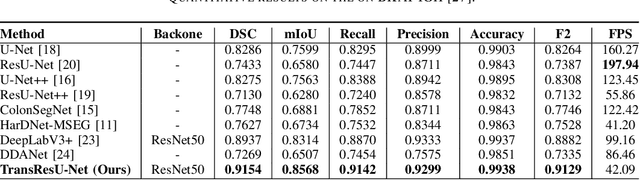

TransResU-Net: Transformer based ResU-Net for Real-Time Colonoscopy Polyp Segmentation

Jun 17, 2022

Colorectal cancer (CRC) is one of the most common causes of cancer and cancer-related mortality worldwide. Performing colon cancer screening in a timely fashion is the key to early detection. Colonoscopy is the primary modality used to diagnose colon cancer. However, the miss rate of polyps, adenomas and advanced adenomas remains significantly high. Early detection of polyps at the precancerous stage can help reduce the mortality rate and the economic burden associated with colorectal cancer. Deep learning-based computer-aided diagnosis (CADx) system may help gastroenterologists to identify polyps that may otherwise be missed, thereby improving the polyp detection rate. Additionally, CADx system could prove to be a cost-effective system that improves long-term colorectal cancer prevention. In this study, we proposed a deep learning-based architecture for automatic polyp segmentation, called Transformer ResU-Net (TransResU-Net). Our proposed architecture is built upon residual blocks with ResNet-50 as the backbone and takes the advantage of transformer self-attention mechanism as well as dilated convolution(s). Our experimental results on two publicly available polyp segmentation benchmark datasets showed that TransResU-Net obtained a highly promising dice score and a real-time speed. With high efficacy in our performance metrics, we concluded that TransResU-Net could be a strong benchmark for building a real-time polyp detection system for the early diagnosis, treatment, and prevention of colorectal cancer. The source code of the proposed TransResU-Net is publicly available at https://github.com/nikhilroxtomar/TransResUNet.